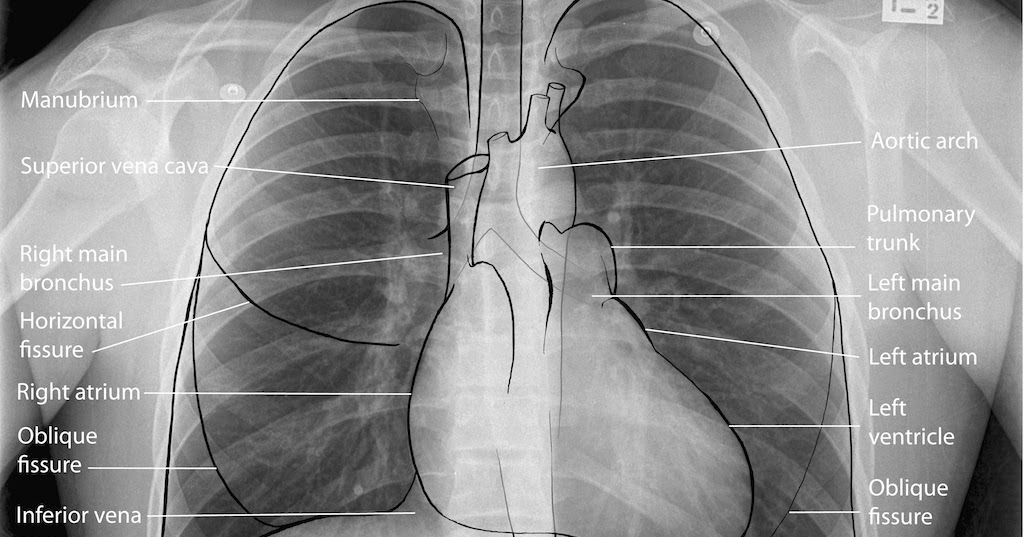

Labeled chest radiographs teaching radiologic anatomy with a level of detail appropriate for medical students.

Major structures are shown in fig. Both lungs should be well expanded and similar in volume. Each of these anatomical structures should be viewed using a systematic approach. Gillian lieberman forthe harvard 62. Note the larger appearing heart on the ap view. The interpretation of a chest film requires the understanding of basic principles. The interpretation of a chest film requires the understanding of basic principles. Labeled chest radiographs teaching radiologic anatomy with a level of detail appropriate for medical students. Therefore, knowing the basics and pathologies in the ed setting is very important. Consolidation, interstitial, nodule/mass, and atelectasis. A collection of anatomy notes covering the key anatomy concepts that medical students need to learn. Look for lung and pleural pathology. In fact every radiologst should be an expert in chest film reading.

Radiology basics of chest ct anatomy with annotated coronal images and scrollable axial images to help medical students and junior doctors learning anatomy. Labeled chest radiographs teaching radiologic anatomy with a level of detail appropriate for medical students. Next, a good inspiration film should show at least the 10th or 11th posterior ribs. Look for lung and pleural pathology. Chest radiographs are the most common film taken in medicine.